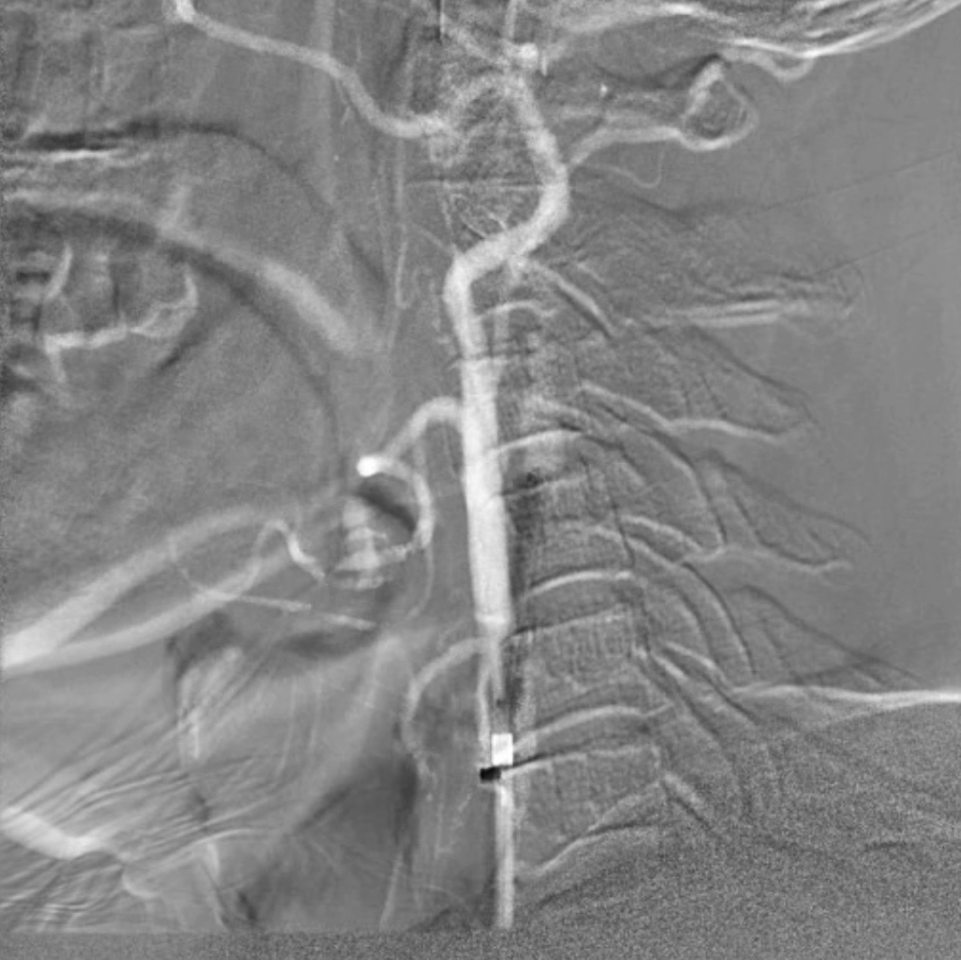

术后评估

血供改善与安全性验证

造影显示:支架膨胀良好,无需后扩张;

颅内血供:左侧颈内动脉血流通畅,因右侧闭塞,左侧成为全脑主要供血通路,血供恢复满意